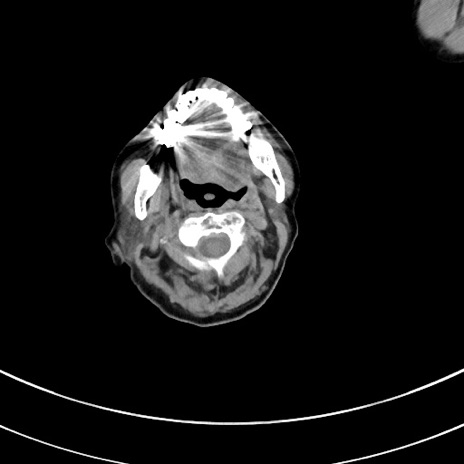

症例33(横断像)

【症例】70歳代 女性

【主訴】心窩部痛

【現病歴】延髄病変の精査・加療にて神経内科入院中。本日より心窩部痛あり。

【身体所見】右下腹部を中心に圧痛と反跳痛あり。

【データ】WBC 10900、CRP 0.02